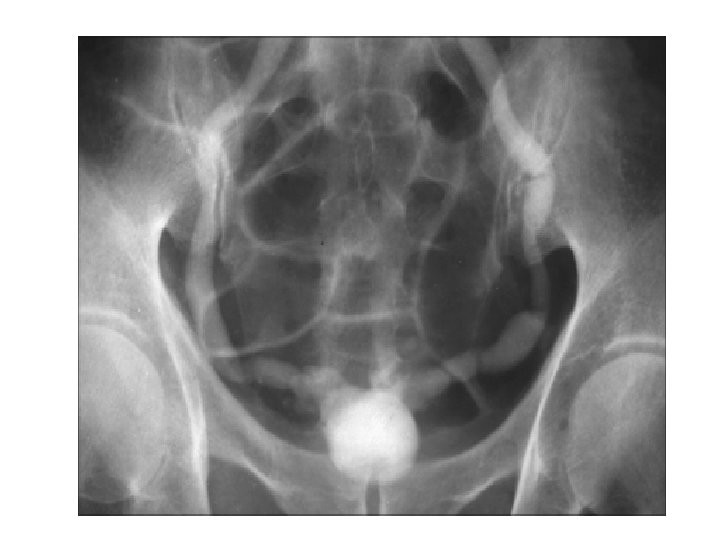

Osteopoikilosis • Uncommon benign sclerosing bone dysplasia with an autosomal dominant inheritance • It is characterized by the presence of dense spots that are round, oval, or lanceolate, with their long axes parallel to the long axis of the bone. They are usually uniformly dense, and are grouped towards the end of long bones and pelvis. • The skull, ribs, and vertebrae are usually spared. The patients may also have disseminated white spots on the skin called dermatofibrosis lenticularis disseminata.